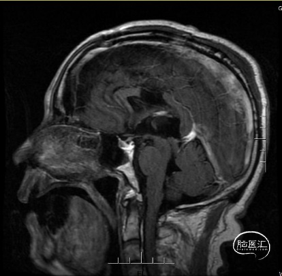

术前影像

术后复查影像

术后MRI提示原肿瘤已全切除,脑室系统形态大小正常,术区无积血,增强术区无明显强化,中线结构居中,余颅内情况基本同前。